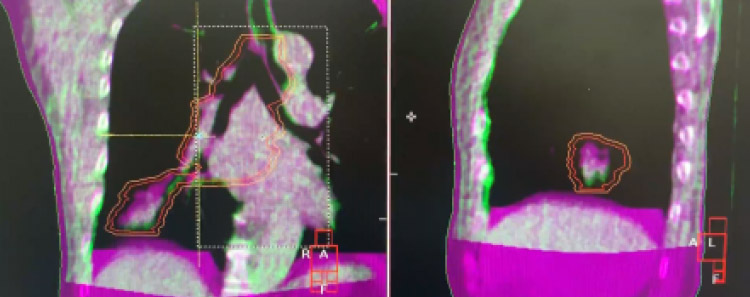

OBIは治療機側⾯に連結したX線透視装置で、治療寝台上で放射線照射を受ける状態での治療位置照合を可能とします。また、回転撮影することにより寝台上で治療直前のCT画像(CBCT︓cone-beam CT)も取得できます。これによりX線透視では⾒えない軟部臓器や腫瘍病巣の動きを詳細に観察することが可能になり、治療の精度をさらに⾼めることができます。

CBCT画像の例(前⽴腺)

治療計画時との画像と治療寝台上でのずれをCT画像で確認内部臓器や腫瘍の動き調節することが可能 精度1mm

CTシミュレータは、治療計画(どのように放射線を照射するか)を⾏うシステムです。体内にある病変と正常臓器情報を取得し、正常組織を避けながら腫瘍に集中して照射できる、より最適な⼿法を患者個々に検討します。また、腫瘍の動きを加味した「4次元CT」の 撮影が可能となり、肺や上腹部のように呼吸により⼤きく動く部位で、腫瘍や正常臓器の動きを考慮した治療計画を⾏うことができます。